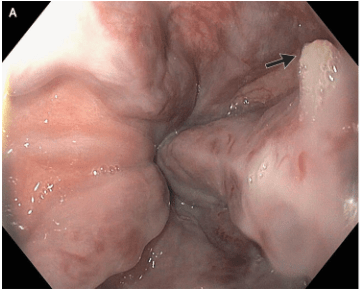

M Najem, E Dong. N Engl J Med 2024;390: e47. Esophageal Varices, White-Nipple Sign, and Portal Hypertensive Gastropathy

This case reported on a 66 year old with cirrhosis and variceal bleeding. “One varix had a “white-nipple sign” (Panel A, arrow), which indicates recent variceal hemorrhage and results from the formation of a fibrin plug at the site of a resolved thrombus.”

“Though not widely mentioned as a stigma of recent variceal hemorrhage, this finding was first reported by Chung and Lewis in 1984 [4]. They described it as a white nipple on top of a varix protruding into the lumen and noted its presence in up to 5% of cases of variceal bleeding. It was thought to represent a platelet-fibrin plug at the site of recent variceal rupture. They noted that dislodgement would be accompanied by jet-like bleeding and called it ‘Mount St. Helens’ sign’ due its volcanic-like eruption…As Chung and Lewis [4] initially suggested, it should ‘alert the endoscopist to take urgent measures to avert a disaster’. Recognizing it as such, attempts to dislodge the lesion must be avoided and endoscopic therapy should be undertaken.”